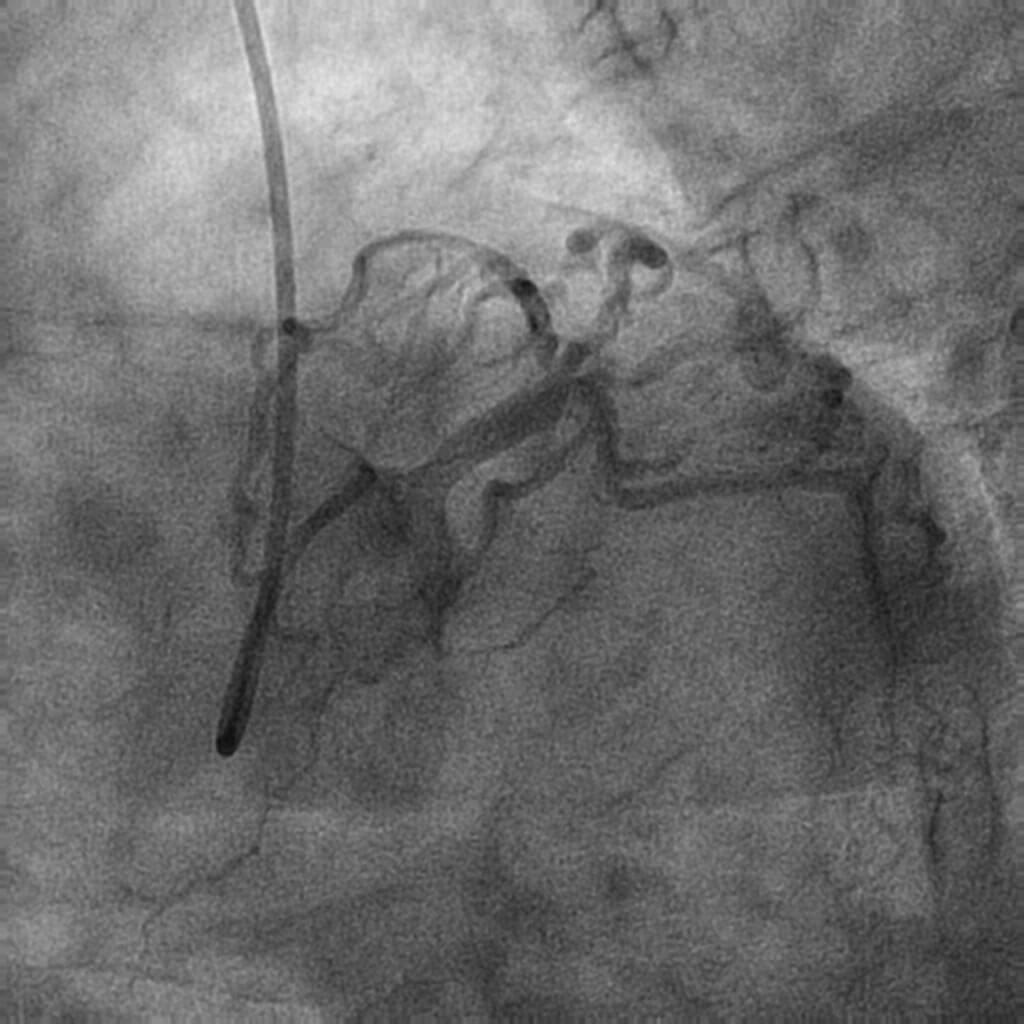

Se completó el estudio mediante coronariografía, en la que se observó enfermedad arterial coronaria del tronco común y de 2 vasos: tronco común largo y calcificado con lesión distal al límite de la significación que afectaba la bifurcación con la descendente anterior, 2 ramas intermedias y la circunfleja; la descendente anterior con lesión grave y calcificada ostial, primera y segunda ramas intermedias con lesiones significativas y calcificadas ostiales, y la circunfleja con lesión moderada ostial (figura 1, figura 2 y vídeo 1 del material adicional) con vaso distal de fino calibre y escaso recorrido. El aortograma mostró una válvula aórtica trivalva y calcificada, con apertura de los velos limitada e insuficiencia aórtica ligera; raíz aórtica y aorta ascendente no dilatadas y sin ateromatosis significativa (figura 3 y vídeo 2 del material adicional). La arteriografía de miembros inferiores mostró un eje ilíaco-femoral no calcificado ni tortuoso, con un diámetro mínimo de 7,3 mm en la arteria femoral común derecha y un diámetro mínimo de 7,7 mm en la arteria femoral común izquierda. Se calculó un riesgo a corto plazo de la Society of Thoracic Surgeons del 10,79%.

Figura 1. Angiografía coronaria en proyección oblicua anterior izquierda caudal que muestra enfermedad del tronco común distal significativa, con afectación de la descendente anterior y de dos ramas intermedias.